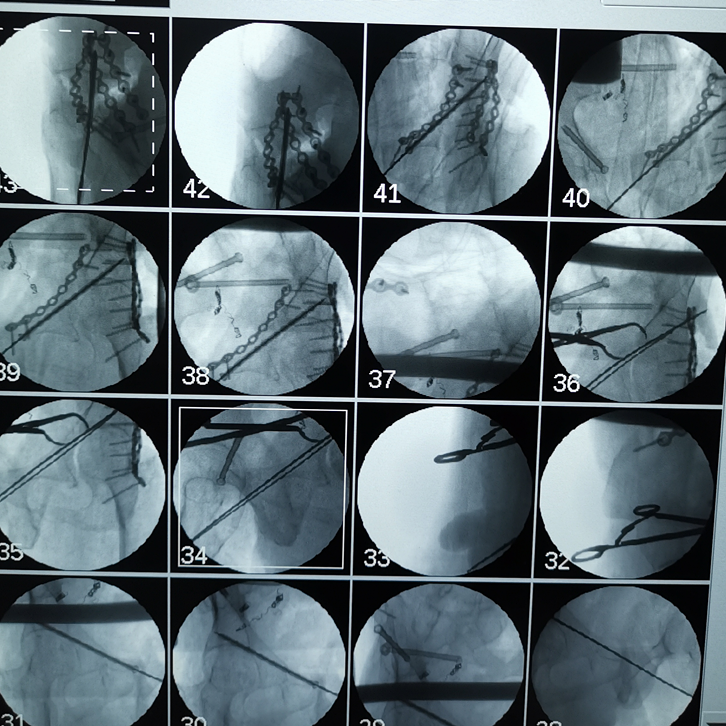

吸痰、冰毯、抗炎、抗凝、氣管切開、下腔靜脈濾器植入……見招拆招,ICU的日日夜夜,在嚴(yán)重創(chuàng)傷并發(fā)癥的狂風(fēng)暴雨中,創(chuàng)傷中心與ICU醫(yī)護(hù)人員的精心照料,為韓大叔撐起了生命之傘。周春峰與周袁平主任節(jié)假無(wú)休,除夕前,還為韓大叔做了雙側(cè)骨盆髖臼骨折確定性手術(shù)(雙側(cè)前后路切開復(fù)位內(nèi)固定VSD引流術(shù))。

雙側(cè)骨盆髖臼骨折前后路手術(shù)